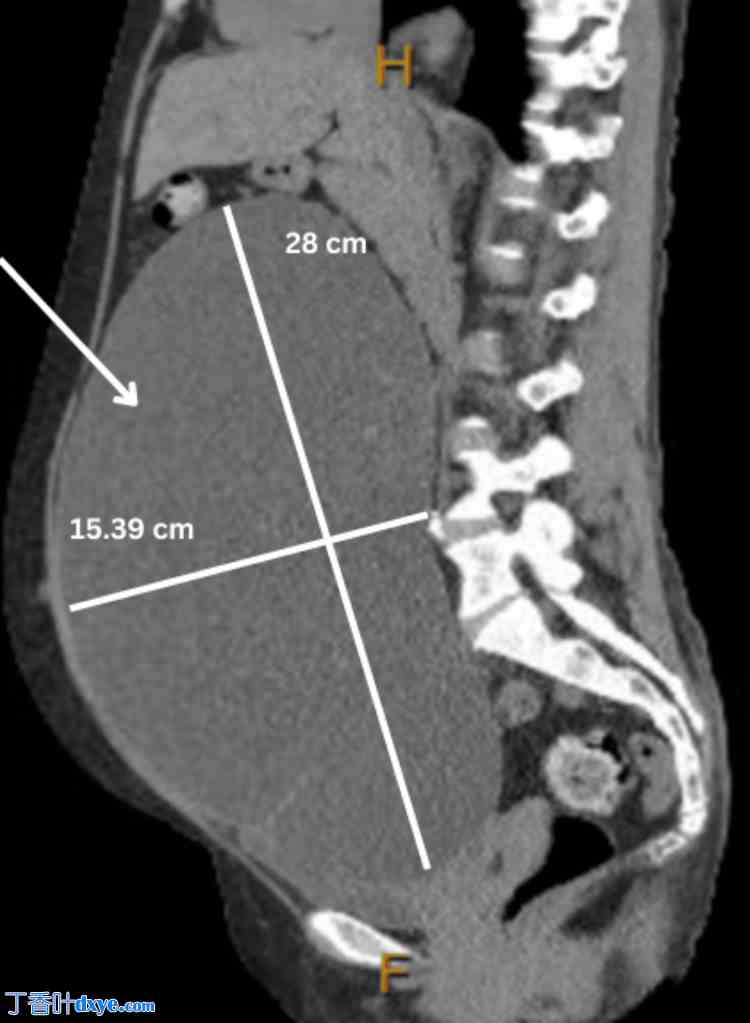

图 3. 右侧边缘性卵巢肿瘤的矢状面 MRI 图像,大小为 28 cm x 15.39 cm。

3.jpg